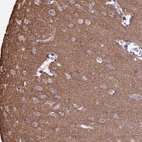

Immunohistochemical staining of human testis shows strong positivity in nucleoli in cells in seminiferous ducts.